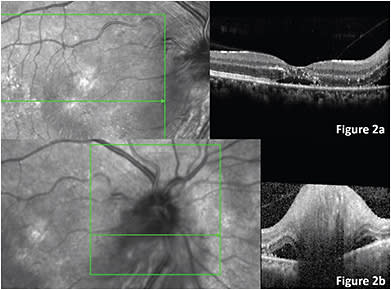

On fundus examination of the OD, optic nerve head (ONH) swelling was found with few peripapillar micro-hemorrhages. In the macula, a star-shaped arrangement of hard exudates was observed. On the left eye, the ONH, macula, and posterior pole showed within normal limits. On general physical exam, oral temperature was 37.5°C (99.5°F) and several skin erosions with fine scaring were observed on both hands and forearms. On spectral domain optic coherence tomography (SD-OCT), important optic disc swelling could be observed, with subretinal fluid inferotemporal to the ONH that extended toward the macula. Diffuse hyperreflective dots between the external limiting membrane and inner nuclear layer were found in the macula, as well as subfoveal subretinal fluid (SRF) (Figures 1 and 2).